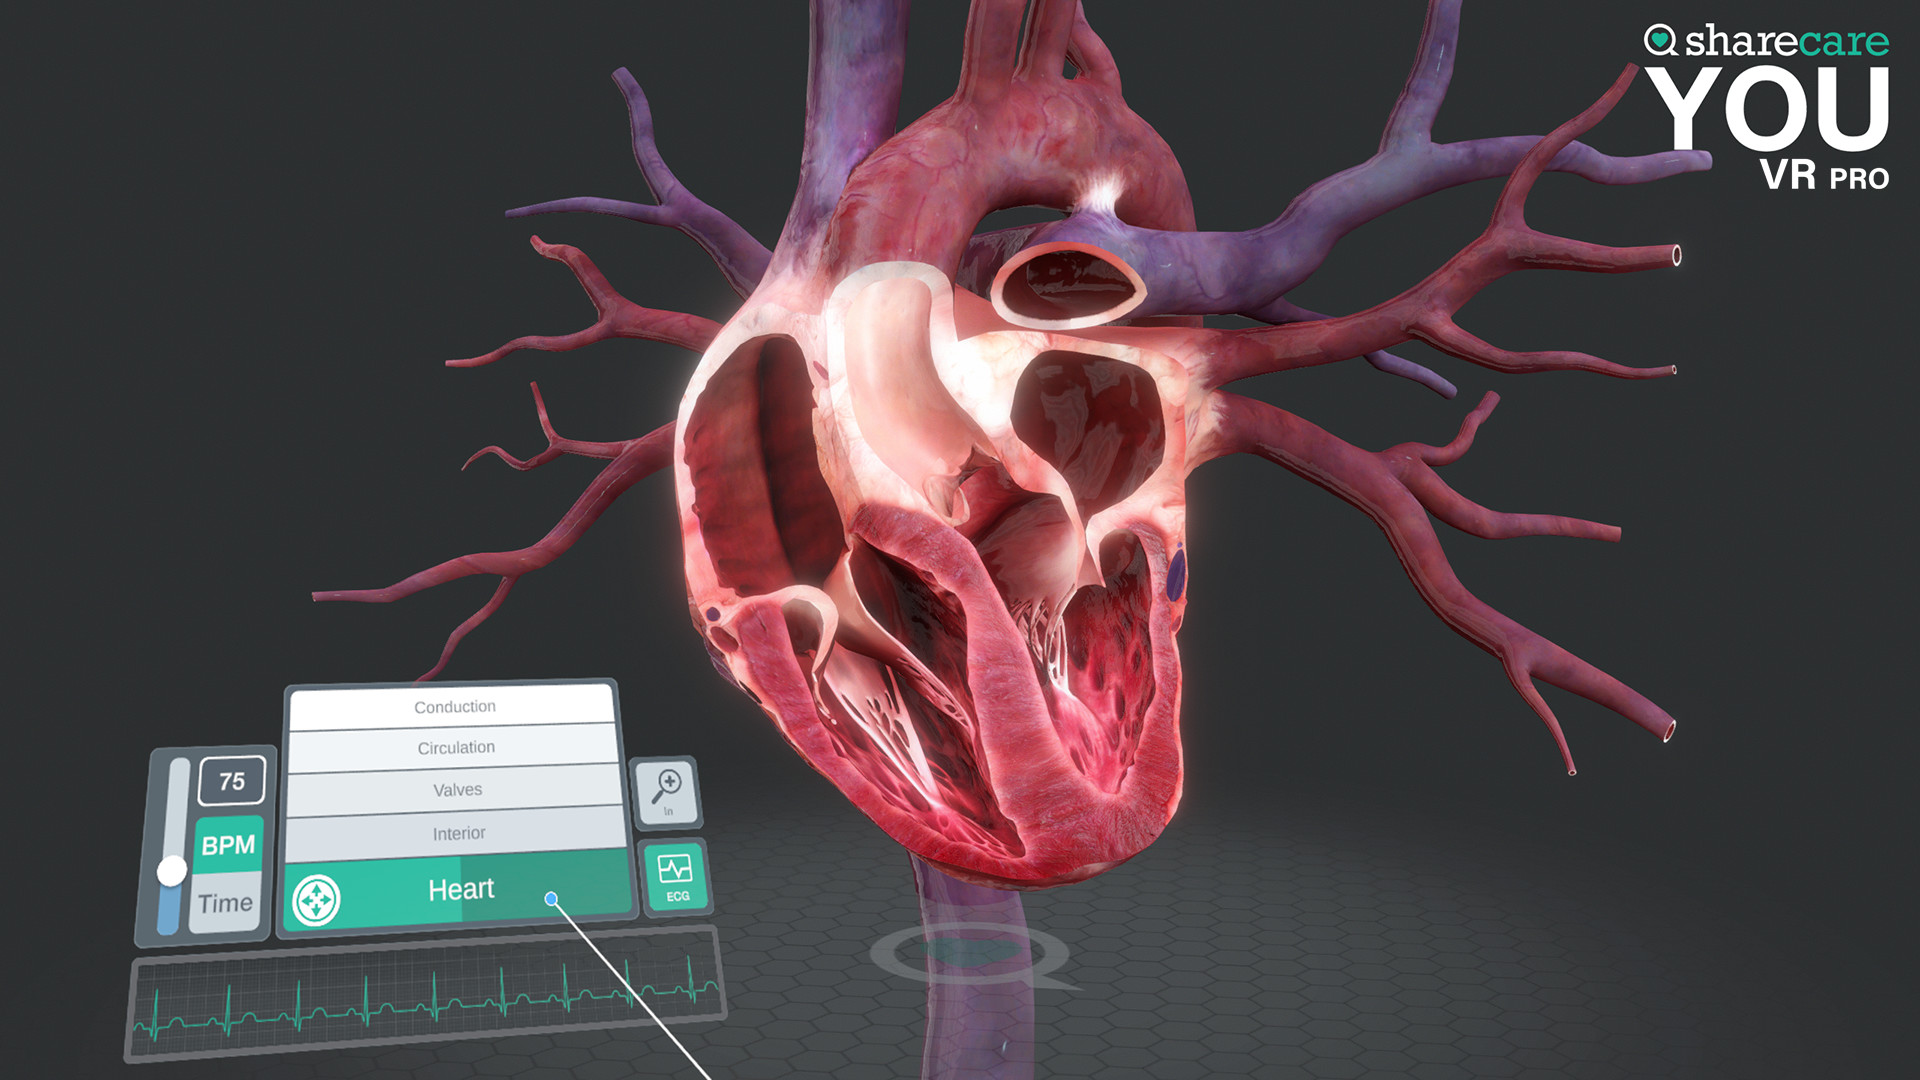

The winner of the 2019 Appy Best VR App is now available on Mac and PC, with more content, bolder graphics, and enhanced features! Sharecare YOU VR is a fully immersive, photorealistic simulation of the human body, enabling anyone to explore its astonishing details in full 360 degrees. Interested in learning about a specific organ? With the click of a button, travel inside, visualize its natural function, and dive deeper. Want to learn even more? Check out the many tags and labels along the way to gain even more information and insight. Easily customize YOU to better understand physiology and simulate disease. You can even personalize our avatars to be a virtual you – your health, your conditions. It really is all about YOU. With YOU VR PRO, users can create visually compelling, high-quality educational content. Build YOU lectures and presentations easily, with the help of video and voiceover recording, and the ability to draw and add your own text. You can also be the star within these videos using our web-cam feature.

- YOU content - an expanding library of over 40 different scenes to explore including anatomy, physiology, conditions, and treatments

- Informative labels and scene information

- Completely updated user interface with unique interactive controls

Looking to use the content for Business Purposes? Get the Sharecare YOU VR Pro version and have the ability to use all the amazing content for Business Purposes. Take advantage of breathtaking graphics and never seen before views of the human body. Your ability to better communicate human anatomy and physiology with your customers and/or students is at your fingertips!